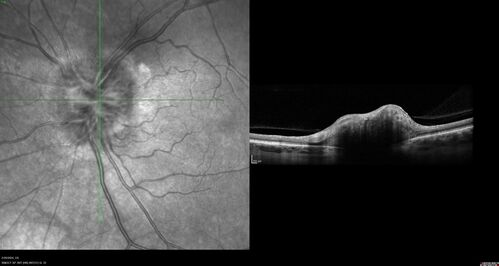

Advanced age-related macular degeneration

87 year old female. Severe macular bleed 15 years ago OD. Now with disciform scar. Left eye has progressing geographic atrophy.

VA OD: HM, OS: 5/200. IOP normal OU